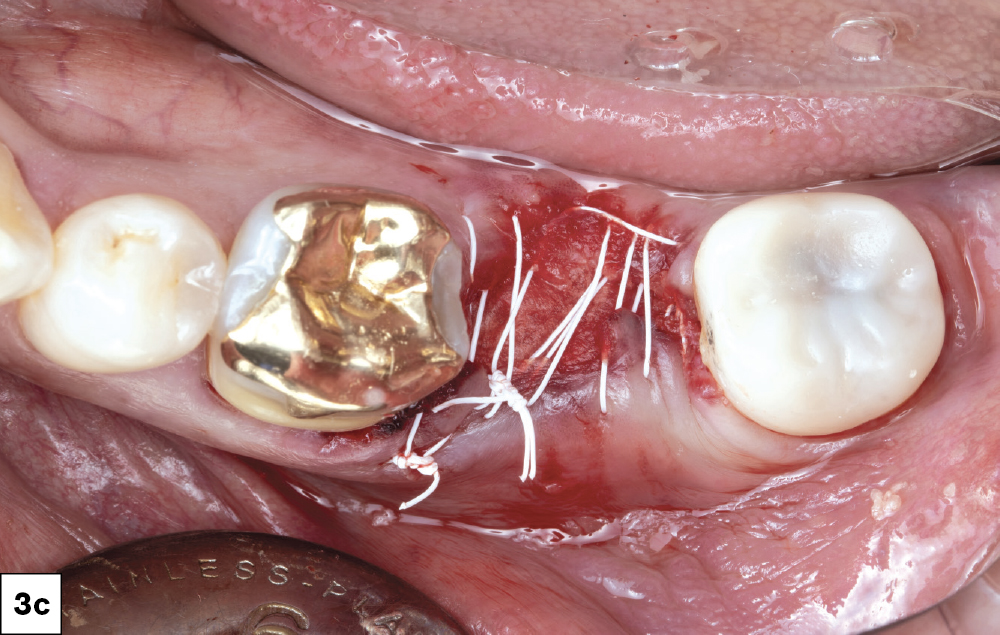

Stitched #18 socket

Figures 3a–3c: Tooth #18 was atraumatically extracted, and all infected tissue was removed using a curette to thoroughly scrape and clean the socket. Newport Surgical™ Mineralized Cortico/Cancellous Allograft Blend was applied to the site with a Newport Surgical Resorbable Collagen Membrane 4-6 added to prevent soft tissue ingrowth (Glidewell Direct; Irvine, Calif.). Biotex™ PTFE Sutures (Glidewell Direct) were used to close the site for a four-month healing process.